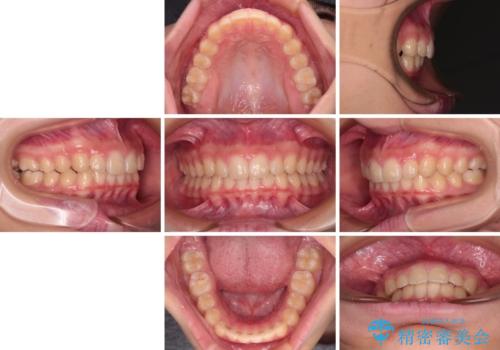

海外で始めたインビザライン 転医手続きにより治療を継続

- ヨーロッパにてインビザライン矯正を始めたものの、日本に転居することになり、治療の継続を希望して来院された患者様です。

治療計画に無理がなく、現地担当医と速やかに連絡が取れるとのことで、インビザライン社での転医手続きを行い、継続して治療を行うこととしました。

舌の突出癖により、上下前歯が非接触となっていたため、トレーニングを徹底的に指導し、安定した咬み合わせにより終了させることができました。